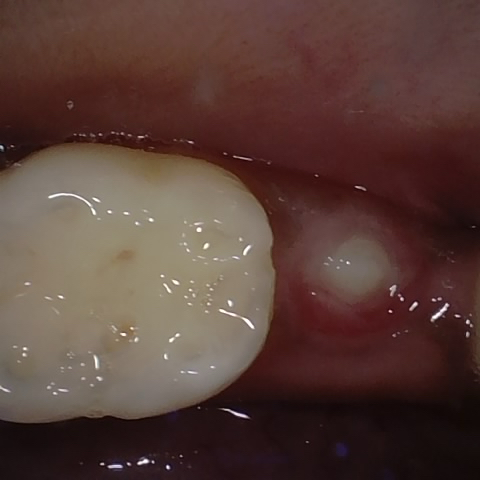

Annotated as "Good"